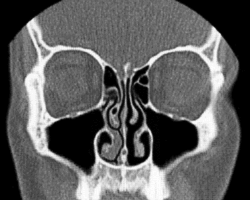

Normal Nose CT Front cross section -

Coronal section of nasal cavities -